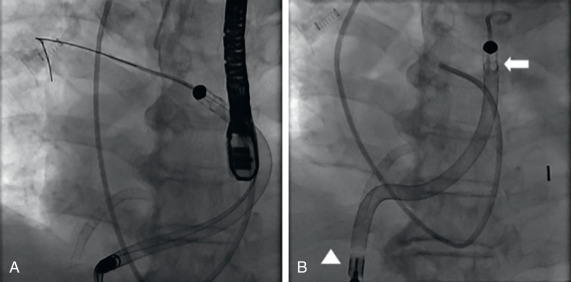

Hình 4. Vị trí đặt thiết bị hỗ trợ thất phải (TP) qua da Impella (Abiomed).

(A) Đưa thiết bị qua da bên phải theo dây dẫn cứng 0.018 qua đường ra thất phải vào động mạch phổi chính. Thủ thuật được thực hiện dưới gây mê toàn thân với hướng dẫn của siêu âm tim qua thực quản. (B) Vị trí cuối cùng của thiết bị hỗ trợ TP, với đường vào của thiết bị nằm dưới chỗ nối tĩnh mạch chủ dưới nhĩ phải (mũi tên) và đường ra của thiết bị nằm trong động mạch phổi chính (đầu mũi tên). Lưu ý mối quan hệ giữa đường ra của thiết bị với ống thông động mạch phổi, một phương pháp đơn giản để xác nhận vị trí thiết bị trên X-quang ngực thường quy.

(Từ Margey R, và cộng sự. Kinh nghiệm đầu tiên với việc cấy ghép thiết bị hỗ trợ thất phải qua da Impella như một cầu nối để phục hồi trong nhồi máu thất phải cấp tính biến chứng sốc tim tại Hoa Kỳ. Circ Cardiovasc Interv. 2013;6[3]:e37–e38.)